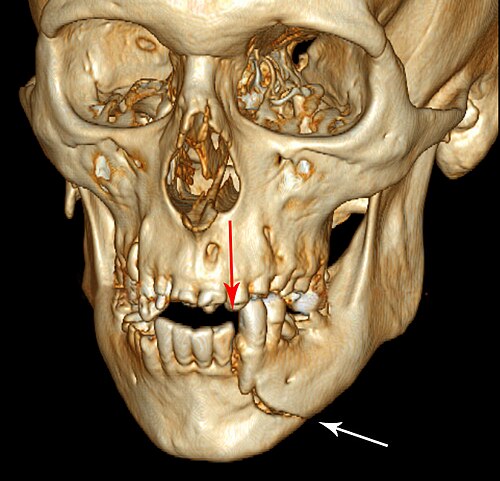

Cone-beam CT phantom of the maxillofacial region showing teeth, alveolar bone, sinuses, nasal cavity, and mandibular...